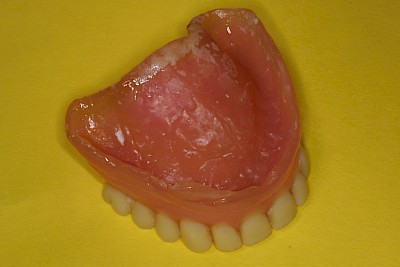

Weiche Beläge lassen sich in den meisten Fällen mit Zahnprothesenbürsten und Zahnpasta entfernen. Auch Reinigungstabletten können hilfreich sein. Haftcreme lässt sich mit Kompressen oder Pflaumentupfern leichter entfernen – sowohl von den Schleimhäuten der Kiefer wie auch von den Prothesen.

Belag

Weiche Beläge oder Speisereste sollten zunächst durch Intensivierung der Prothesenpflege beseitigt werden. Harte Beläge, die sich auch mit Zahnprothesenbürsten entfernen lassen, können durch einen Zaharzt mit speziellen Prothesenreinigungsgeräten (Ultraschallbad) entfernt werden.

Weichbleibende Unterfütterungen werden durchgeführt, wenn es immer wieder zu Prothesendruckstellen kommt. Allerdings lassen sich weichbleibende Unterfütterungsmaterialien nicht so gut reinigen. Es kommt schneller zu Belagsbildungen und Pilzbefall. Mit der Zeit können zudem die Materialien verspröden, was die Belagsbildung weiter begünstigt. Dann spätestens ist es sinnvoll und notwendig, den Zahnarzt zu verständigen.